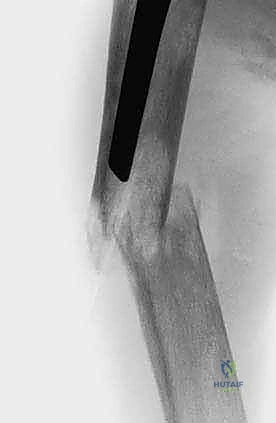

1. التثبيت الوقائي الداخلي (Prophylactic Internal Fixation)

إذا أظهرت الأشعة أن العظم ضعيف جداً وعلى وشك الانكسار، يقوم الدكتور هطيف بوضع أسياخ نخاعية معدنية (Intramedullary Nails) أو شرائح ومسامير متطورة داخل العظم لتدعيمه ومنع الكسر قبل حدوثه. هذه الجراحة الاستباقية توفر على المريض آلاماً مبرحة ومضاعفات خطيرة.

2. استئصال الورم وتغيير المفاصل (Tumor Resection & Endoprosthetic Arthroplasty)

في الحالات التي يدمر فيها الورم المفصل بالكامل (مثل مفصل الورك أو الركبة)، يقوم الدكتور هطيف باستئصال الجزء المصاب من العظم والورم معاً، واستبداله بمفصل صناعي خاص بالأورام (Megaprosthesis). بفضل خبرته الواسعة في تغيير المفاصل، يستطيع المريض المشي في اليوم التالي للعملية!

4. الجراحة الميكروسكوبية ومناظير 4K

لتقليل التدخل الجراحي والنزيف، يستخدم الدكتور هطيف تقنيات المناظير الحديثة بدقة 4K والميكروسكوب الجراحي، مما يسمح برؤية الأعصاب والأوعية الدموية بوضوح فائق، وهو ما يقلل من مضاعفات الجراحة ويسرع من التئام الجروح.

المرحلة الثانية: الإجراء الجراحي (Intra-operative)

- تتم الجراحة في أحدث غرف العمليات المجهزة والمُعقمة في صنعاء.

- يتم استخدام تقنيات وقف النزيف المتقدمة.

- تُجرى العملية بأعلى معايير الأمانة الطبية، حيث لا يغادر الدكتور هطيف غرفة العمليات إلا بعد التأكد التام من استقرار التثبيت العظمي والمفصلي.